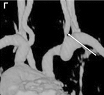

Ангиография – это наиболее точный метод, позволяющий увидеть на экране рентгеновской установки то, что происходит внутри сосуда (рис. 4). С него начинают, если пациент уже перенес инсульт и по данным УЗДГ МАГ выявлены значимо ограничивающие кровоток сужения сосуда, то есть высок риск повторения инсульта. Исследование проводится в специальной операционной, оснащенной ангиографической установкой.

Рис. 4. Критические стенозы внутренней сонной артерии (ангиография).

Во время ангиографии очень тонкий катетер вводится в артерию на ноге и продвигается к сосудам шеи. Место введения катетера будет обработано антисептиком и обезболено. После этого через катетер вводится контрастное вещество, делающее видимыми артерии, питающие мозг, под рентгеновскими лучами. Врач произведет съемку артерии. Если есть стенозы или окклюзии артерий – они будут обнаружены.

Рис. 4. Критические стенозы внутренней сонной артерии (ангиография).Во время ангиографии очень тонкий катетер вводится в артерию на ноге и продвигается к сосудам шеи. Место введения катетера будет обработано антисептиком и обезболено. После этого через катетер вводится контрастное вещество, делающее видимыми артерии, питающие мозг, под рентгеновскими лучами. Врач произведет съемку артерии. Если есть стенозы или окклюзии артерий – они будут обнаружены.